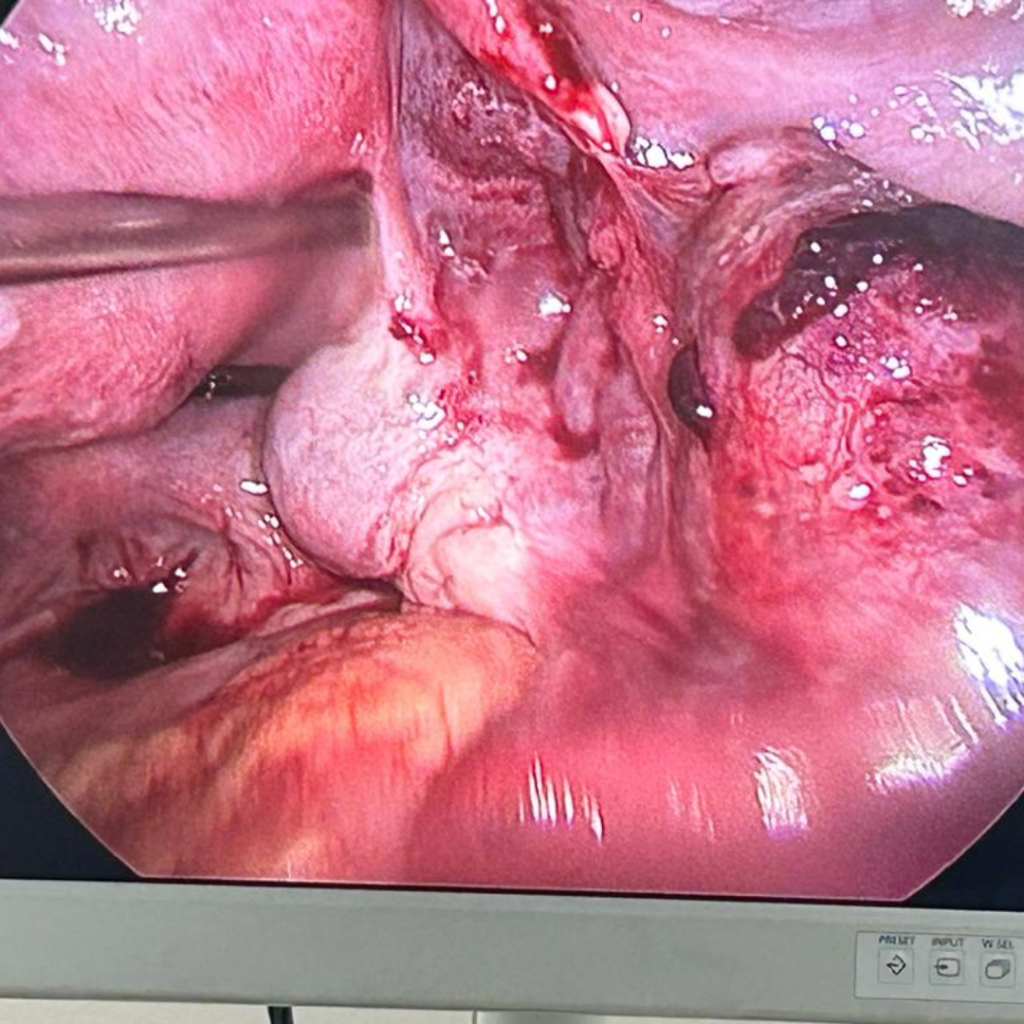

Laparoscopic clearance of ectopic pregnancy